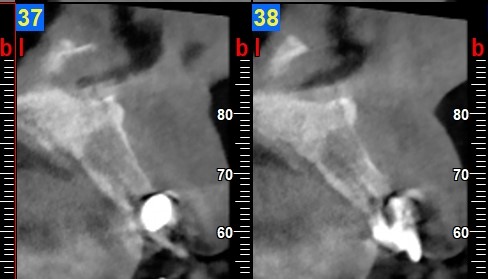

Al test di vitalità gli elementi 21 e 22 risultavano non vitali e all’esame radiografico endorale presentavano un’area di rarefazione periapicale molto estesa (Figura 2).

In accordo con il piano di cura veniva eseguito il trattamento endodontico di 22; dopo circa tre mesi veniva eseguito un ulteriore controllo radiografico che evidenziava una riduzione della lesione periapicale soprattutto a carico del 22 (Figura 3) mentre questa permaneva a carico del 21, per il quale veniva programmata l’estrazione.

Sei mesi dopo, la verifica radiologica CBCT (Figura 7) evidenziava un recupero di radio densità (circa 400 HU) per cui veniva inserito un impianto Biomet-3I Osseotite Tapered Certain di 4 x 13 mm (Figura 8) con torque di inserimento di 20 Ncm.